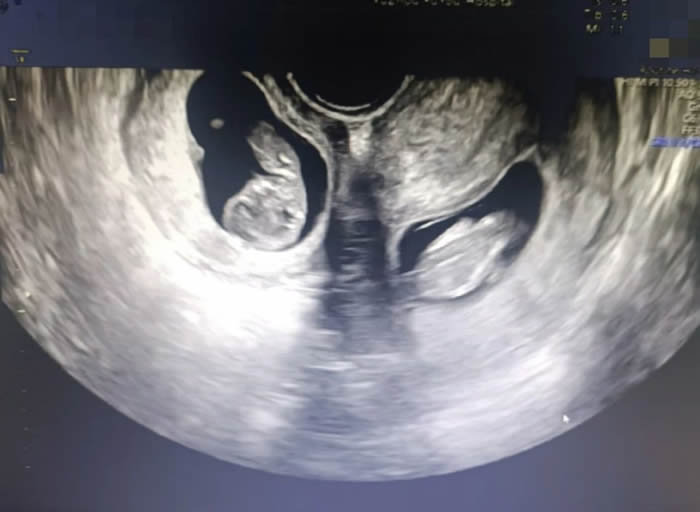

更令人意外的是,早孕期超聲提示,曉曉腹中竟有兩(liǎng)個胎兒(ér),且兩(liǎng)個孩(hái)子各居“一室(shì)”,互不幹擾(rǎo)。“在我近30的職業生(shēng)涯中,還從未遇到過(guò)雙子宮雙胞胎的孕婦。雙子(zǐ)宮女性妊娠風險非常多,很可(kě)能會(huì)出現早產(chǎn)、胎兒生長受限、子宮破裂等情況,每種風(fēng)險都不容小覷。”產科九病區主任吳惠瑩如是說。

當天急診(zhěn)值班主任沙小龍(lóng)接診時發現,曉曉胎膜早破,宮內羊水已所(suǒ)剩無幾,而且(qiě)兩個胎兒均存在胎位不正的問題,已(yǐ)失去保胎機會,需要立刻進行剖宮產手術。考慮到雙子宮(gōng)易造成子宮破裂,大出血等風險,產(chǎn)科九病區緊急聯絡血庫、新生兒科、產房、麻醉科、超聲科等多學(xué)科聯合會(huì)診,做好各項應(yīng)急準(zhǔn)備。

7點50分,一場生命與時間的賽跑拉開序幕。與普通的雙胎剖宮(gōng)產手術不同,此次手術需要分別在曉曉的兩個子宮上切口取出胎兒。

早(zǎo)早等(děng)在一旁的新生(shēng)兒(ér)科(kē)醫生立刻為兩(liǎng)個孩子進行檢查,隨後轉入新生兒病房進行救治。為了預防產後出血,取出龍鳳胎後,沙小龍醫生第一時間用藥促進子宮(gōng)及時收縮,兩(liǎng)個子宮緊(jǐn)緊貼在一起,形成了一個完(wán)整的心型。